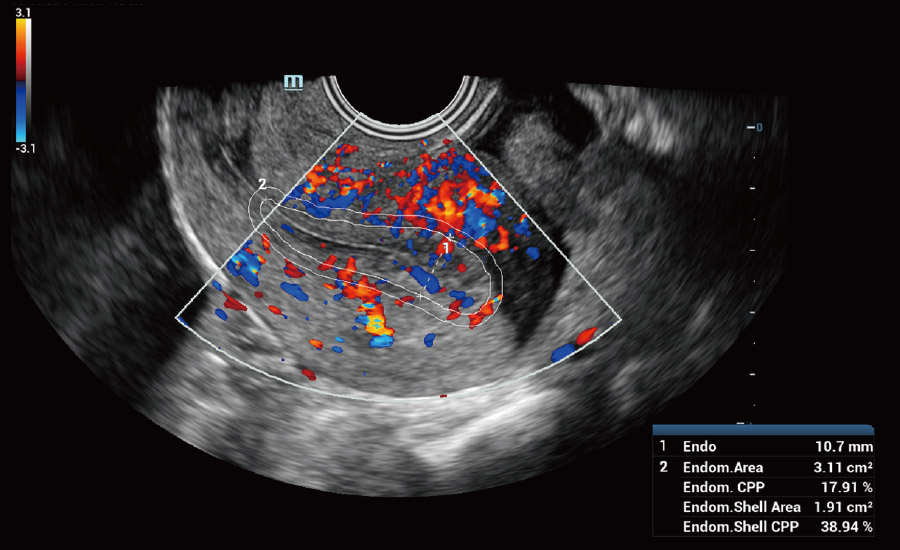

UMA (angiografia ultramicroscĆ³pica)

A tecnologia inovadora elimina as limita??es das tradicionais imagens com Doppler. Com resolu??o espacial e sensibilidade de fluxo ultra-altas, permite a detec??o de perfus?es de fluxos muito sutis e lentos, ampliando assim a aplica??o clĆnica da avalia??o qualitativa e quantitativa do ultrassom no cĆ©rebro fetal, rins, placentas, endomĆ©trios, ovĆ”rios etc.

UMA ā Fluxo uterino e endometrial